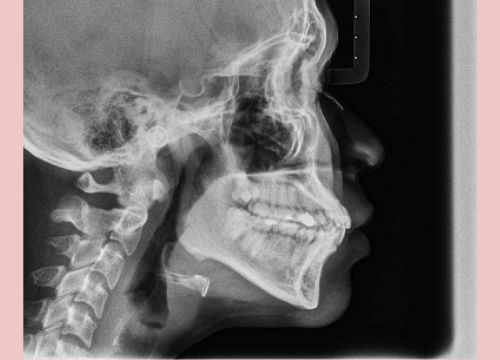

There are several different treatment options to correct a deep bite. Your dentist or orthodontist would take a look at your mouth, palpate your tissues and perform an X-ray known as lateral cephalogram to check your bite. After coming to a diagnosis, the dentist would come up with a treatment plan for your condition.